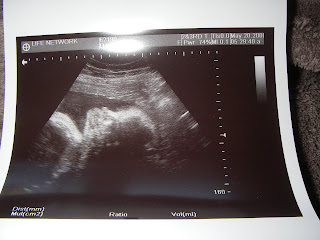

Thanks to Life Network Santa Barbara we got to do an ultrasound this afternoon. They called us this morning to see if we would be willing to volunteer my belly to teach one of their nurses their new ultrasound machine. We went in and found out that Aliyah is tall like daddy, weighs 4.7 lbs and that my due date is right on time for the first week of July.

Here are a few of the pictures!

Aliyah's profile (mouth closed)

Aliyah's profile with her mouth opened and is practicing swallowing (see the white ball in her mouth-that's her tongue!)

Aliyah's profile with her mouth and eyes opened.